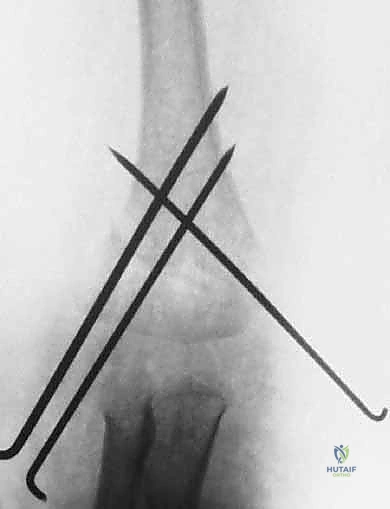

2. العلاج الجراحي: الرد المغلق والتثبيت بالأسلاك (CRPP)

هذا هو المعيار الذهبي لعلاج كسور النوع الثاني غير المستقر، والنوع الثالث، والنوع الرابع. وهو الإجراء الذي يبرع فيه الأستاذ الدكتور محمد هطيف.

* الرد المغلق (Closed Reduction): يعني إعادة العظام المكسورة إلى مكانها الطبيعي دون الحاجة لعمل شق جراحي كبير لفتح الجلد. يتم ذلك من خلال حركات يدوية دقيقة يقوم بها الجراح.

* التثبيت بالأسلاك عبر الجلد (Percutaneous Pinning): بعد إعادة العظم لمكانه، يتم إدخال أسلاك معدنية دقيقة (K-wires) عبر الجلد لتثبيت العظم ومنعه من الحركة حتى يلتئم.